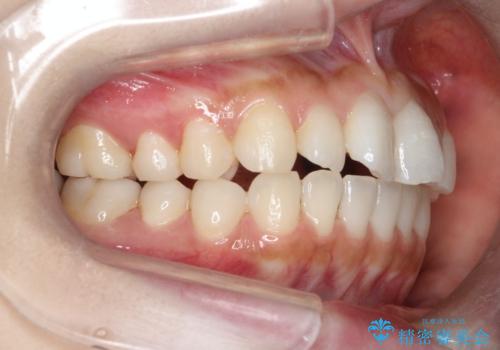

【インビザライン】矮小歯を有する方の治療②

- 前歯の凸凹を主訴に来院されました。

左上の前歯が元々小さいため、前歯の真ん中が揃わないことを伝えた上で矯正治療を開始しています。

スペースを作るために遠心移動ろIPRをおこなて治療を行いました。